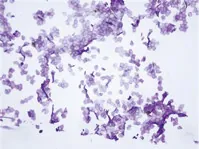

通常,要进行皮肤状况评估,需要进行胶带剥离试验。在胶带剥离试验中,用一块胶带将皮肤剥离,然后对染色的角化层细胞进行评估。

认为角化层细胞面积是反映翻转速度的一个指标。如果对皮肤施加强烈的外部刺激,周转速度会加快,从而使角化层细胞面积变小。另一方面,在老化细胞或代谢功能下降的情况下,周转速度会下降,从而使角化层细胞面积增大。

此外,干燥皮肤经常会出现多层剥落。这表明角质化层细胞剥离了多层,应该一次剥离一层。

磁带剥离评估的示例

在下面的例子中,使用KEYENCE的All-in-One荧光显微镜BZ-X800,通过胶带剥离,观察角质层细胞从皮肤上剥落。通过测量角质化层的细胞面积和多层剥落层的比例,可以评估皮肤的状况。这些测量也可以用来量化多少营业额是提高了化妆品。然而,使用传统方法进行这些测量非常耗时,减少了可以进行的实验数量,从而限制了数据的可靠性。

BZ系列的细胞计数功能可以用来轻松地测量角化层细胞的平均面积和多层剥落层的比率。